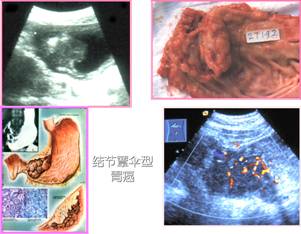

右图为结节蕈散型胃癌.彩超示内部血流丰富.

图片尺寸301x234

第三版课本)蕈伞型降结肠癌上面两幅图像显示蕈伞型结肠癌,结肠腔内

图片尺寸370x359